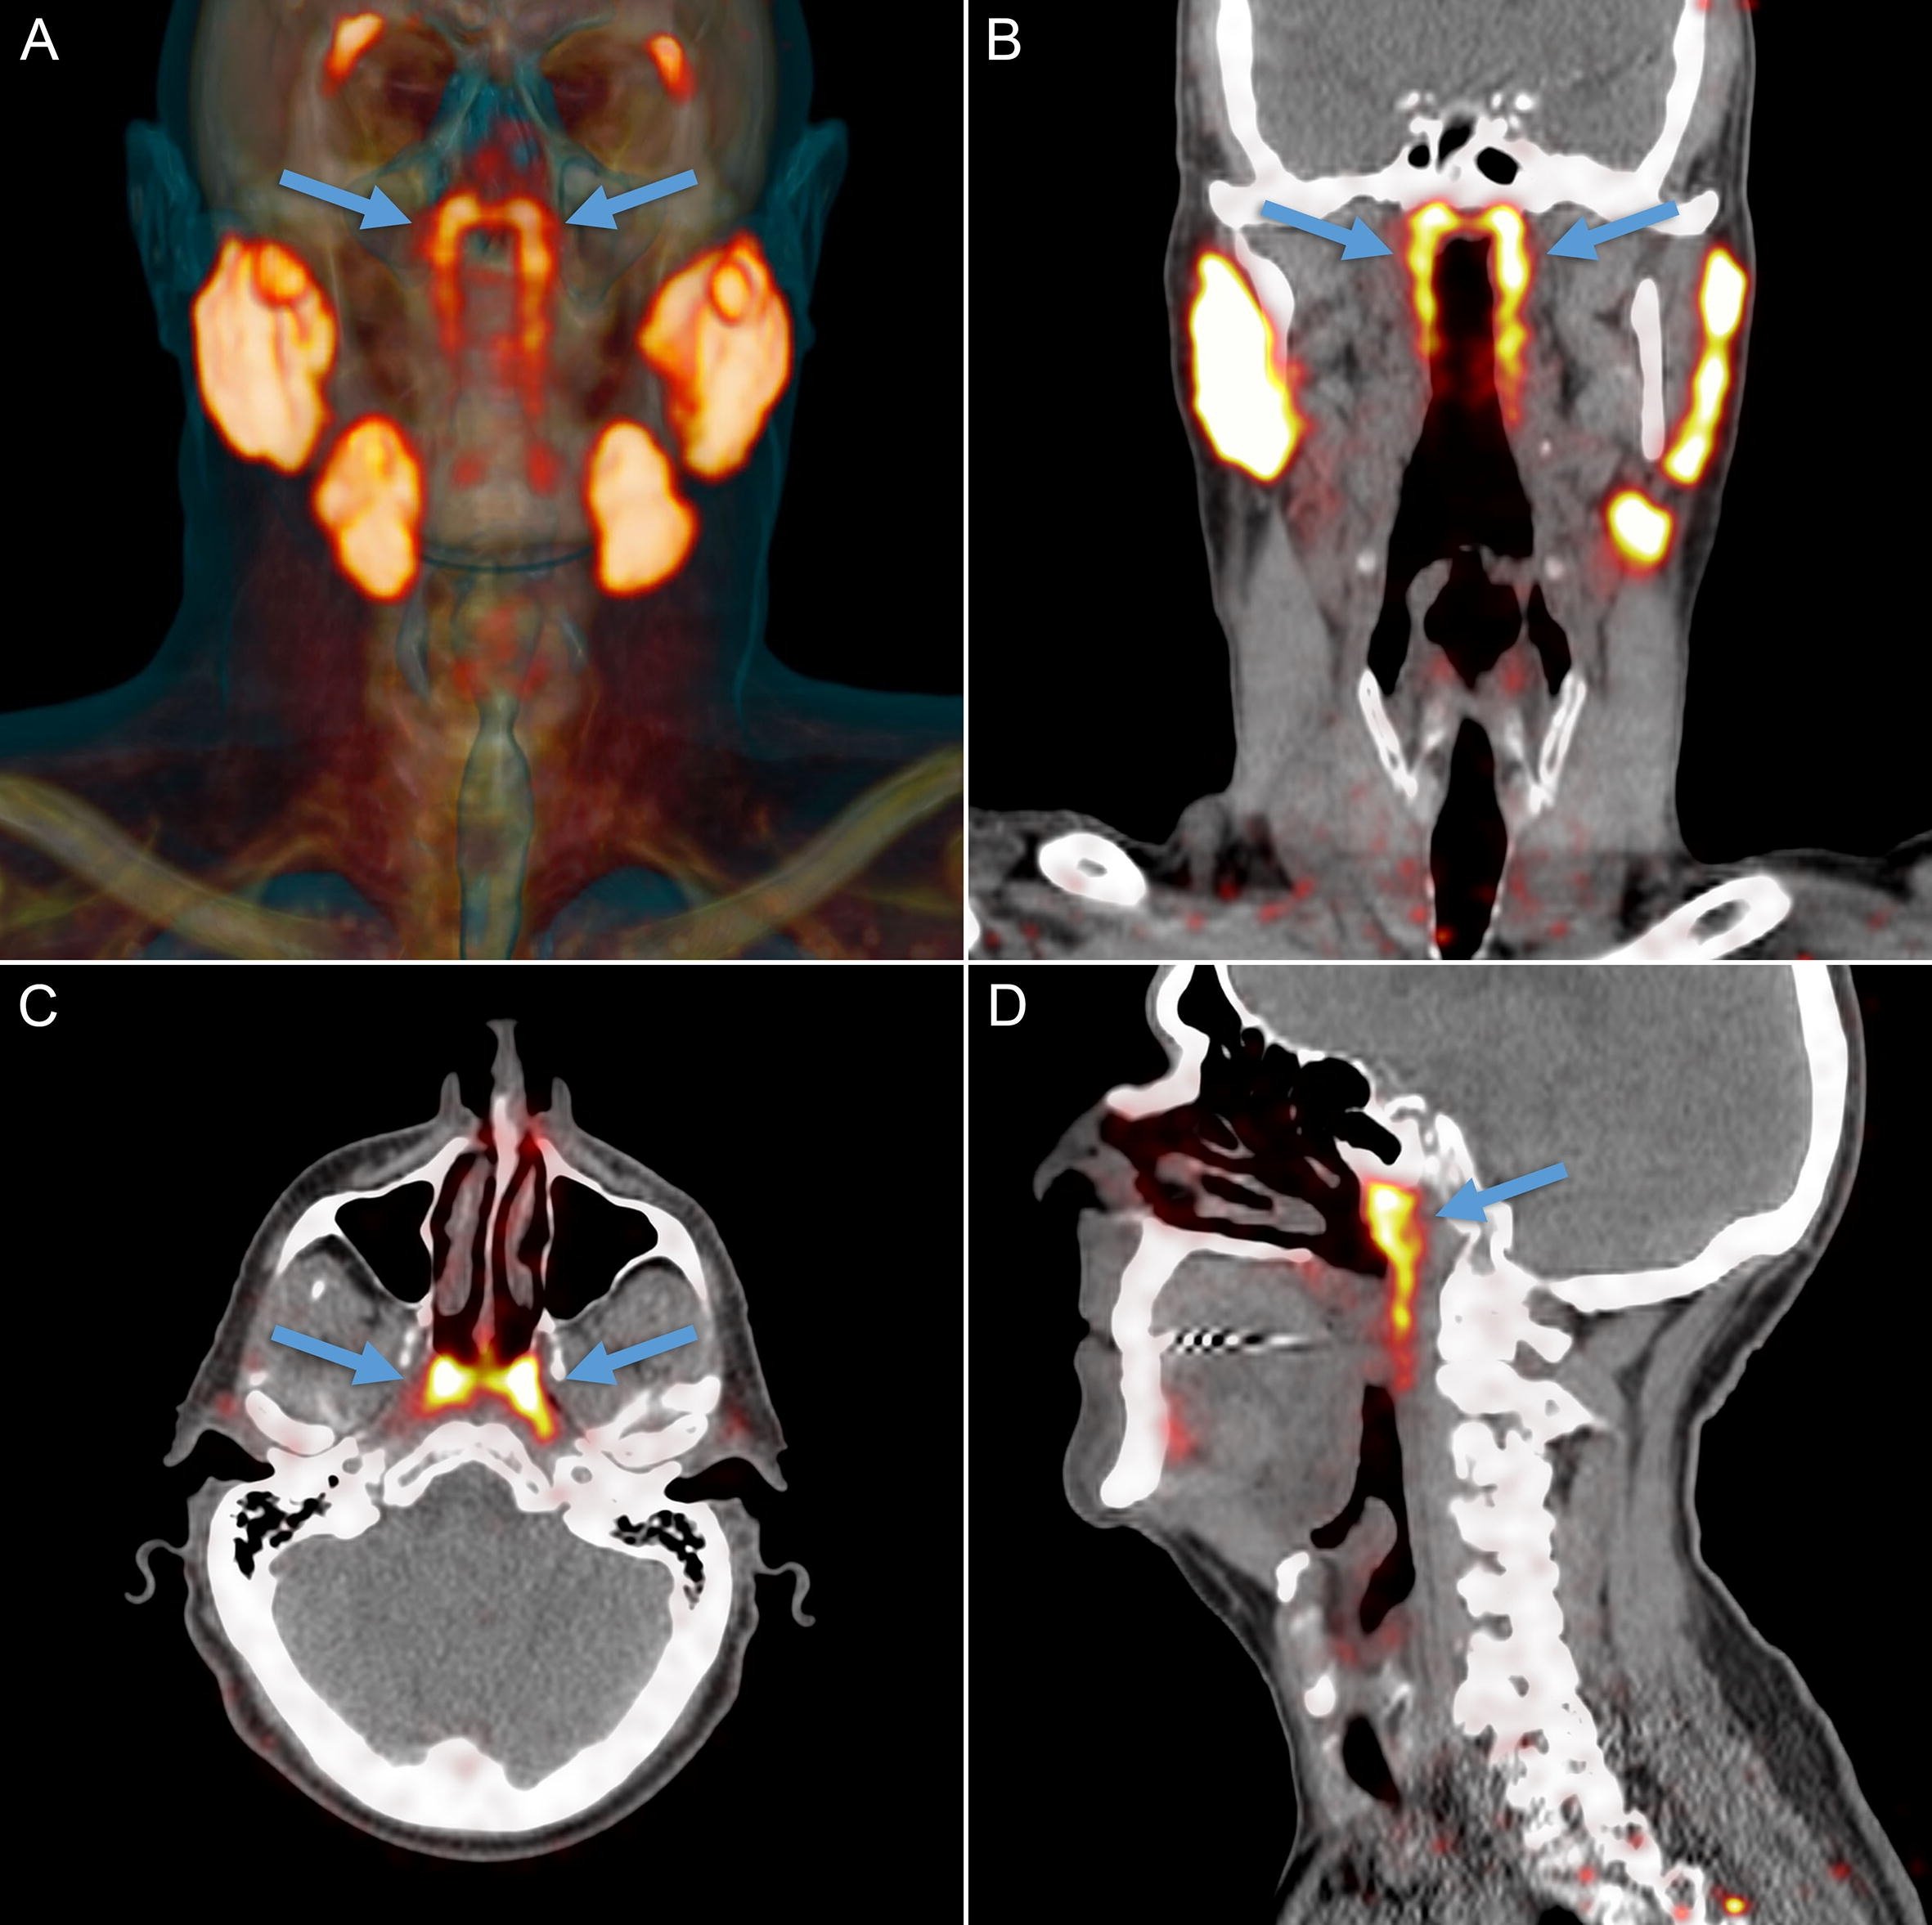

Head and neck imaging involves evaluation of complex anatomical structure including temporal bone, orbit & oral cavity. 3Tesla MRI scans helps in the detail evaluation of related pathological abnormalities of neck organs.